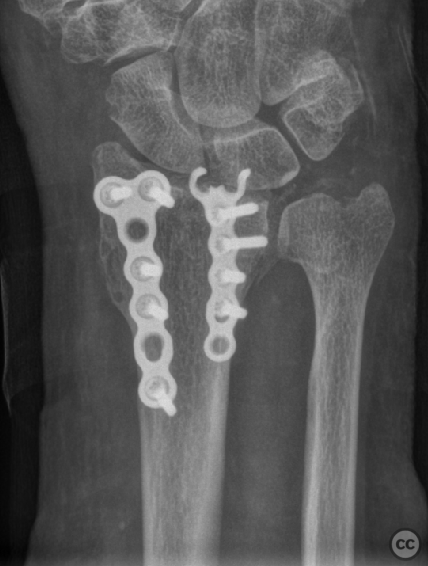

Multifragmentary Distal Radius Fracture with Flipped Ulnar Articular Margin

Clinical Details

Clinical and radiological findings:  A 72-year-old female sustained a multifragmentary, dorsally displaced distal radius fracture after a fall down stairs. Initial reduction revealed a 180-degree flipped fragment of the volar ulnar articular margin, unreducible by closed means. There was no mention of associated neurovascular compromise or open injury. Radiographs and intraoperative fluoroscopy confirmed the presence of a multifragmentary intra-articular fracture (AO/OTA 23-C3), with a flipped volar ulnar fragment and radial styloid impaction. The distal radioulnar joint alignment was restored postoperatively.

Orthopaedic implants used:   - 1.0 mm Kirschner wire (provisional fixation) - 1.8 mm Kirschner wire (scaphoid traction) - 2.0 mm Stryker mini fragment T-plate (cut/shaped as hook plate) - 2.4 mm T-plate (radial styloid fixation)